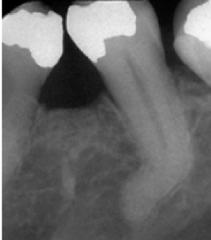

periapical abscess

-Pain, swelling, fistula, slight extrusion of tooth at root -radiographically thickening of PDL and periapical radiolucency ACUTE

periapical granuloma

-asymptomatic, tooth sensitive to percussion, slight extrusion of tooth -radiographically: slight thickening PDL and periodontal radiolucency CHRONIC